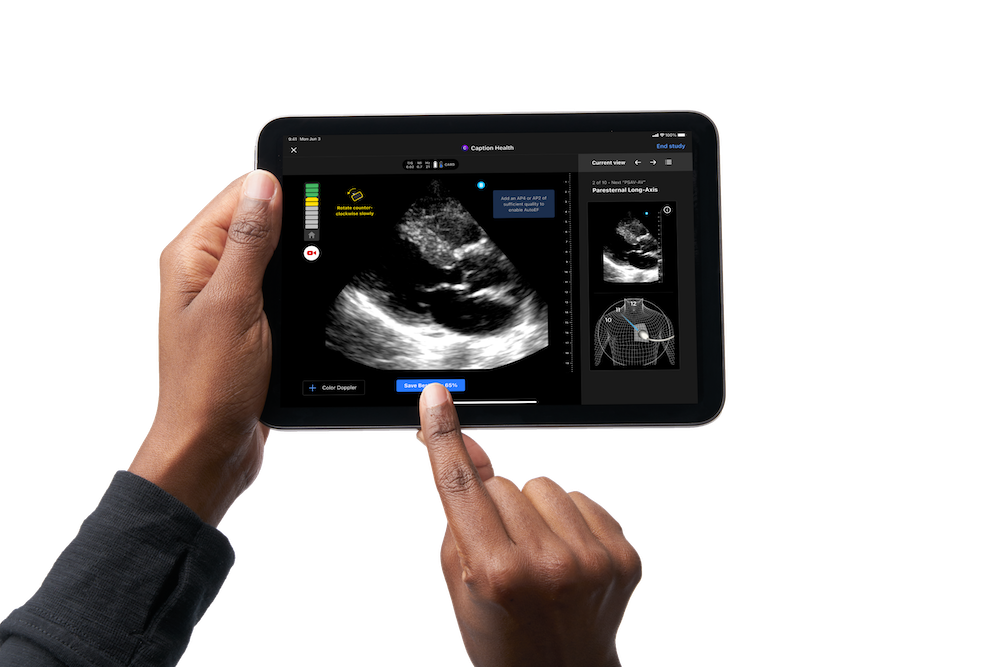

Ultrasound is a powerful tool for imaging the heart, as it is noninvasive, relatively fast, and accessible and can be done at the bedside. But conducting a cardiac ultrasound exam requires a skilled clinician with extensive training. You have to know what you’re looking for and how to move the ultrasound probe to get there. The Caption Health AI tries to solve for this by providing real-time guidance, which can be especially helpful for novice ultrasound users. Caption Health has trained the AI to recognize a diagnostic-quality cardiac image, and the software tells the user, via instructions on the screen, how to move or rotate the probe so they can acquire that optimal image. “It’s like you’re with an expert user who has been doing ultrasound their whole life,” says Yoder. “It’s intuitive.”

It also makes conducting an ultrasound exam easier for people who aren’t experts. GE HealthCare plans to integrate the Caption Health software with its existing ultrasound systems, including the handheld and more affordable Vscan Air. “In some instances, clinicians who do not conduct ultrasound scans every day may need additional support to perform efficient, accurate scans,” says Yoder. “For any healthcare provider who isn’t doing an ultrasound multiple times a day, it needs to be easy to use.”